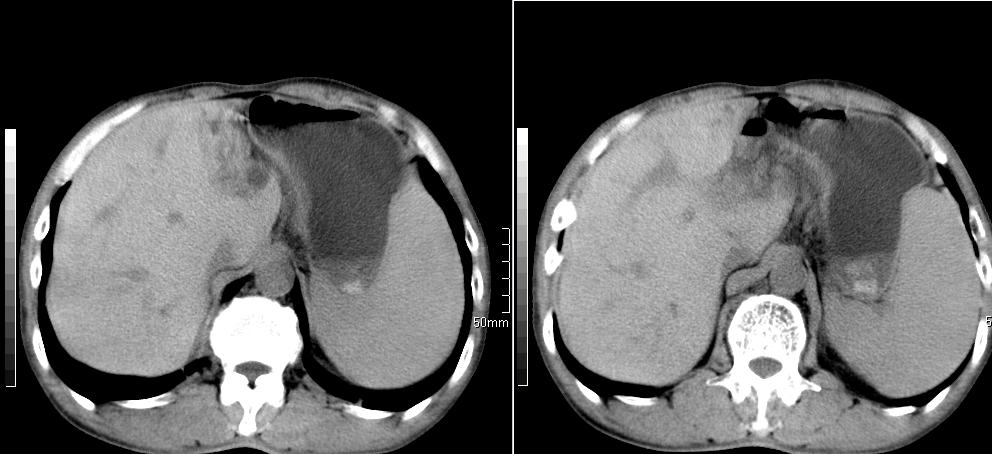

标题: CT26769:男,58岁,腹胀、腹部不适一年余 [打印本页]

标题: CT26769:男,58岁,腹胀、腹部不适一年余

肝右叶后段见小片状略低密度影,边缘不清,轻度强化,内见小血管影通过同,延迟期为等密度,考虑局灶性脂肪浸润。需与血管瘤鉴别。另有胆囊炎、脾大。

1 慢性胰腺炎并假囊肿形成。2 慢性胆囊炎并累及肝边缘!

1)考虑慢性胰腺炎并假性囊肿形成。2) 慢性胆囊炎。3)肝内胆管扩张。

1肝内胆管扩张,性质待定,2慢性胰腺炎胰管扩张,胰腺颈部假囊肿,3肝左叶低密度为小囊肿,4胆囊炎。